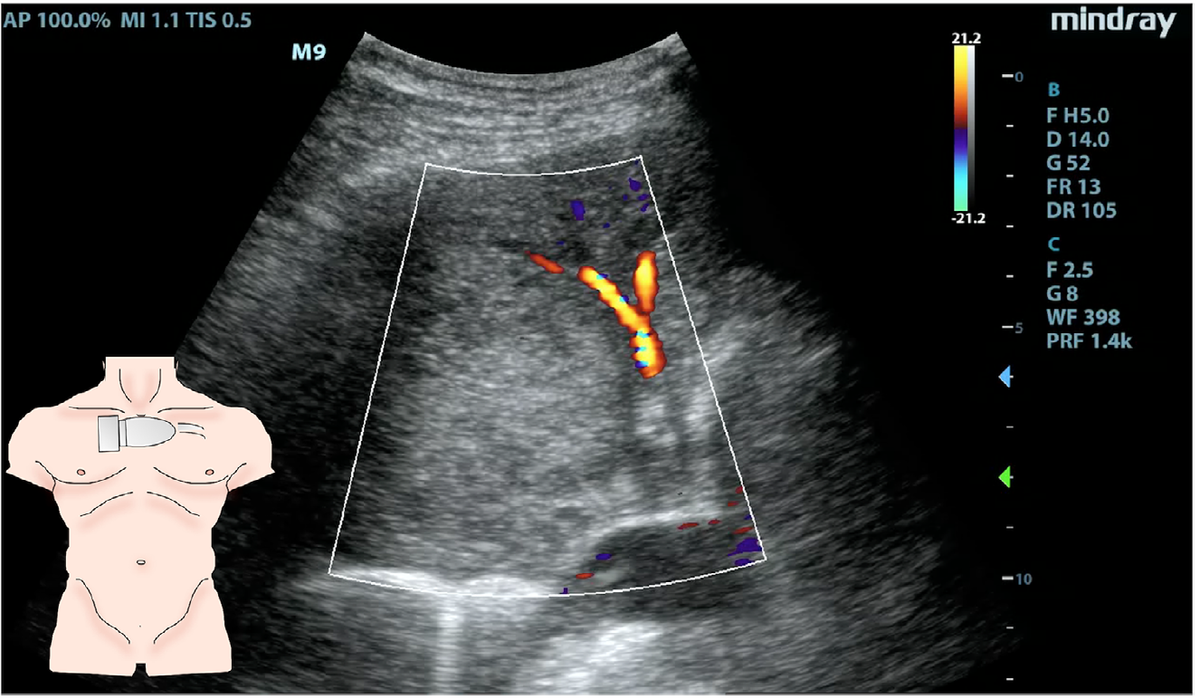

・超音波により肺野に不均一な腫瘤と血流増加が認められた

・超音波検査ではレントゲンで検出できないPancoast腫瘍を同定できることがある

(Chest. 1988 Jul;94(1):124-8./Pain Med. 2016 Dec;17(12):2437-2438.)

・超音波ではレントゲンでは指摘できない腫瘍を同定できることがある